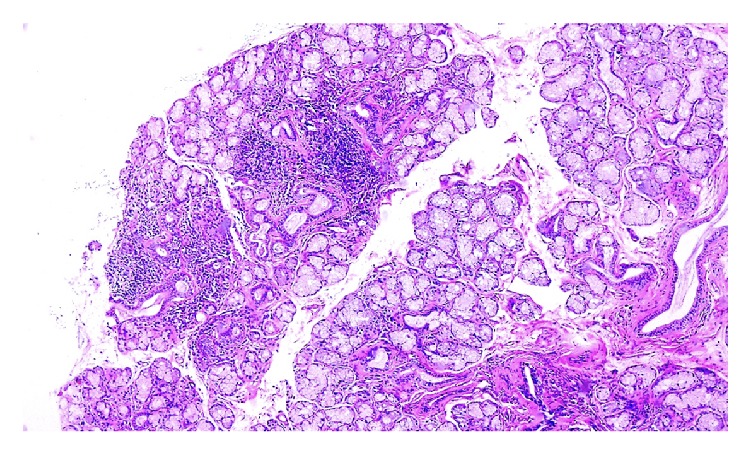

入院时的生命体征是体温36.3℃,心率每分钟54次,呼吸频率每分钟20次,室温下血氧饱和度97%,毛细血管血糖103g/dL,血压100/60mm/Hg。体格检查发现深部肌腱反射整体减弱,近端和远端肌力Lovett评分为3/5,舌干,舌下唾液池缺失。实验室试验见表1。小涎腺活检如图1所示。根据所有的实验室结果,诊断为pSS的远端肾小管酸中毒(RTA)。静脉注射氯化钾

图1小涎腺活检的全景照片。观察到慢性淋巴细胞局灶性涎腺炎。